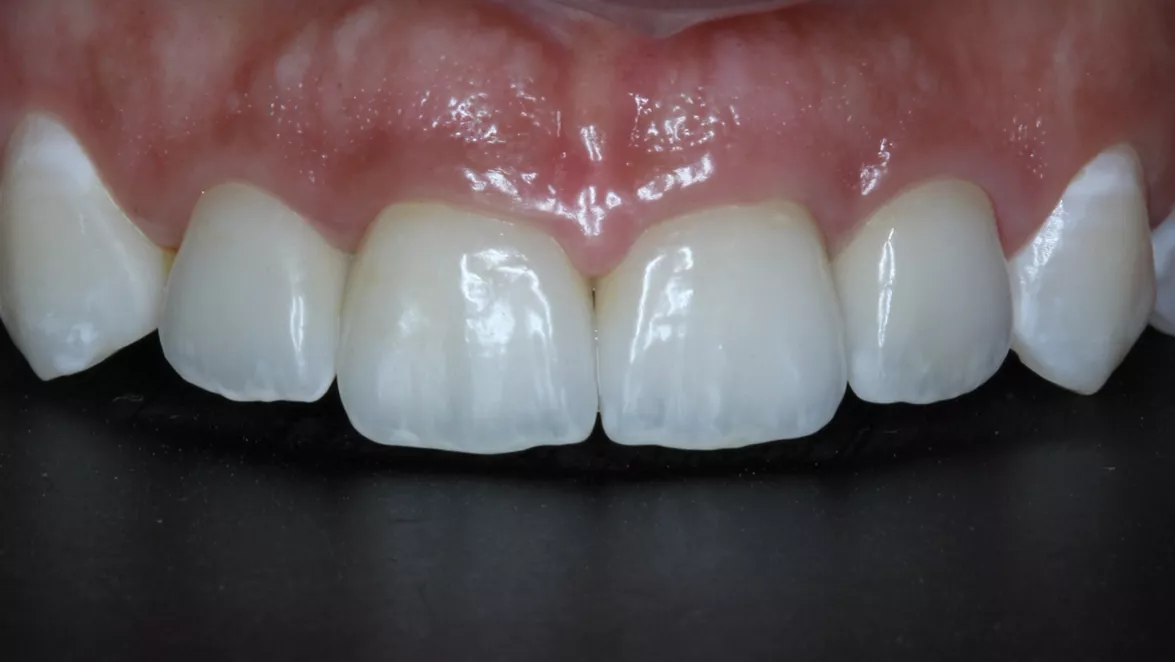

24 - Immediate provisionalization in fresh alveolus with alteration of the gingival phenotype

Dr. Elcio Marcantonio Junior